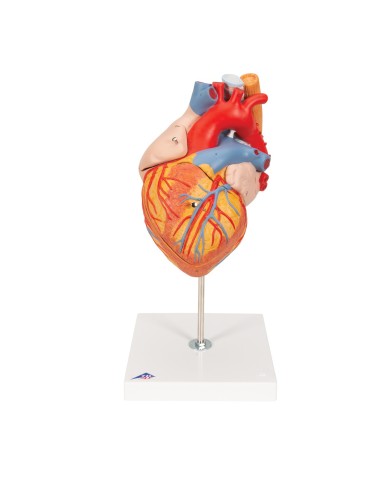

Su base removibile

Modello di cuore di alta qualità scomponibile in 5 parti

Modello di cuore di alta qualità scomponibile in 5 parti

Realizzato in stampa 3D ad elevatissima risoluzione a colori.